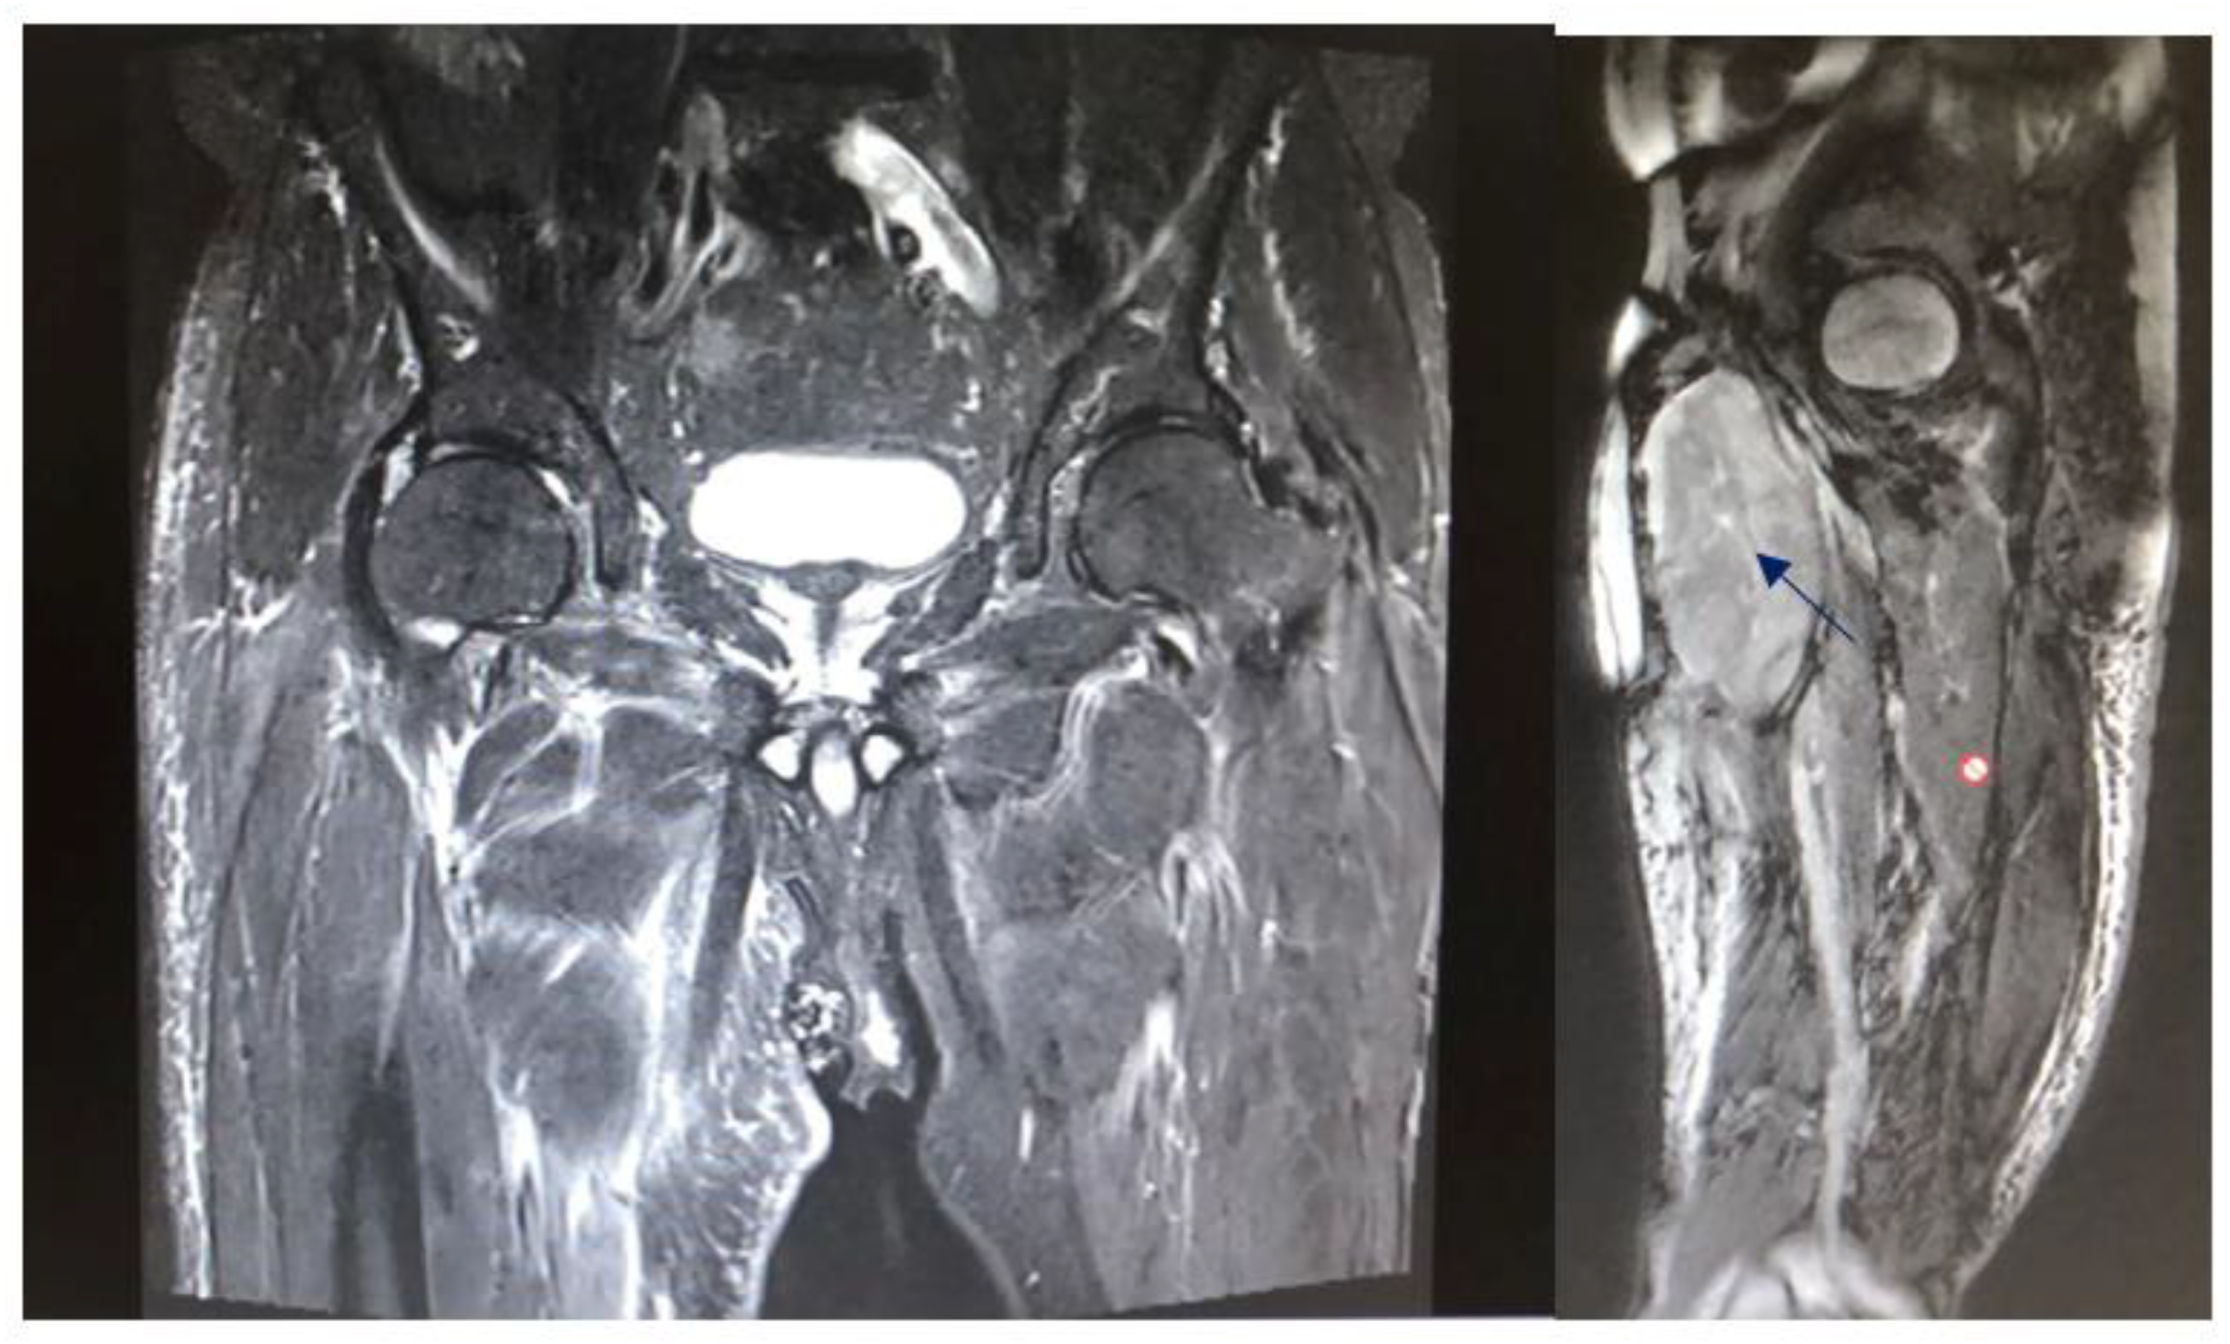

4. Results